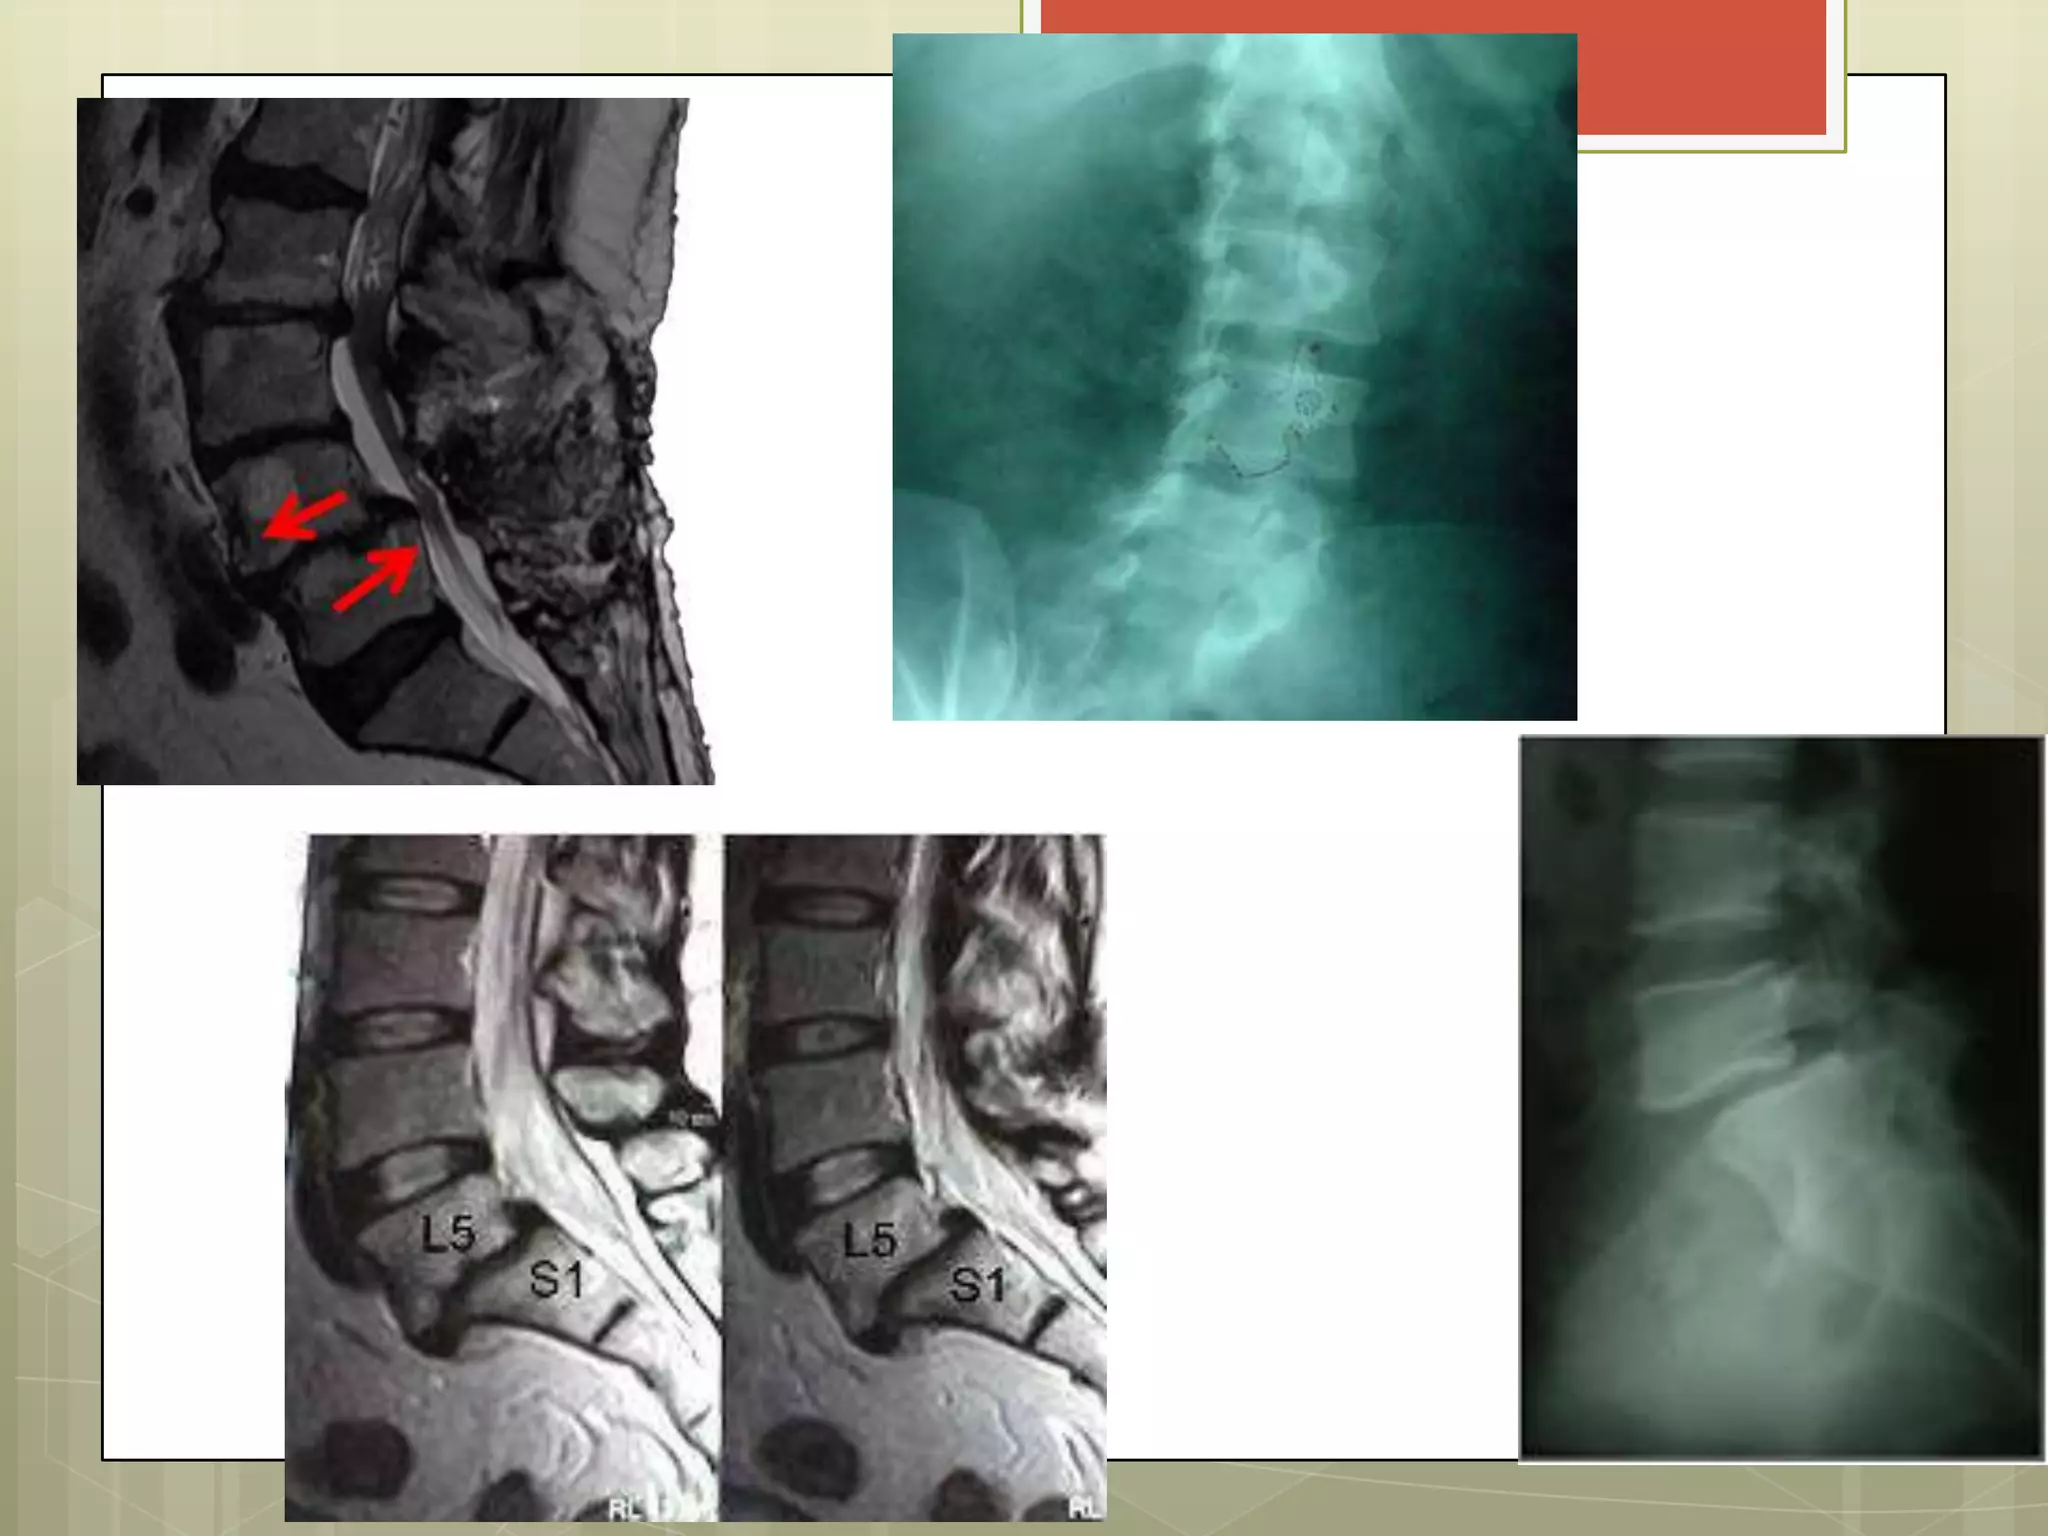

Espondiloartrosis L5 – S1

“Picos de loro”

IMAGENOLOGIA

RAYOS X:

AP. LAT Y OBLICUA        osteofitos

ESPONDILOLISTESIS

Deslizamiento de una vértebra

CLASIFICACIÓN

Grado I     <25 %

Grado II    26 - 50 %

Grado III   51 - 75 %

Grado IV    76 -l 100 %

Por grado de desplazamiento

Espondiloartrosis L5 –S1 “Picos de loro”